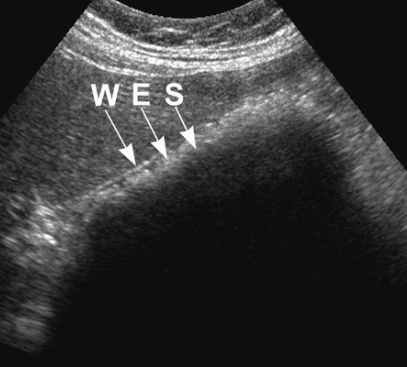

- Wall-echo-shadow (WES) triad = double arc shadow sign